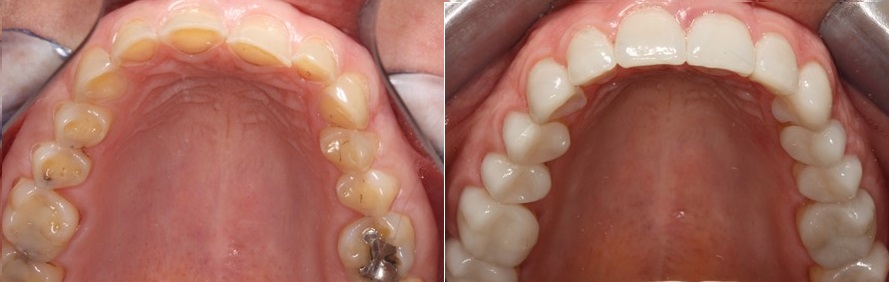

Σε επόμενο στάδιο κατασκευάσαμε όψεις πορσελάνης στα πρόσθια δόντια της άνω γνάθου. Στην φωτογραφία βλέπουμε τα δόντια πριν και μετά την αποκατάσταση με όψεις πορσελάνης.

Με την τεχνική αυτή δεν αφαιρούμε καθόλου την οδοντική ουσία. Τα δόντια δεν τροχίζονται, αλλά προστατεύονται ανάμεσα σε δύο αποκαταστάσεις, μια από την πλευρά της υπερώας και μια από την πλευρά των χειλιών. Δημιουργούμε με τις αποκαταστάσεις ένα sandwich, που επιτρέπει στα δόντια να διατηρούν την ακεραιότητα τους και προστατεύονται. Έτσι δεν χάνουν περισσότερη οδοντική ουσία από αυτή που ήδη είχε χαθεί από την διάβρωση.

Στην φωτογραφία που ακολουθεί βλέπουμε την εικόνα των δοντιών της ασθενούς πριν και μετά την συγκόλληση των όψεων ρητίνης και πορσελάνης στα πρόσθια δόντια και των επένθετων πορσελάνης στα οπίσθια δόντια της άνω γνάθου.

Η εικόνα των δοντιών της άνω γνάθου πριν και μετά την αποκατάσταση